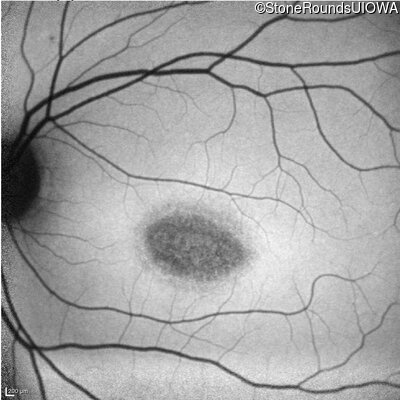

Infrared Fundus Photograph - Right - 20/125 sc

Exemplar

Infrared Fundus Photograph - Left - 20/125 sc